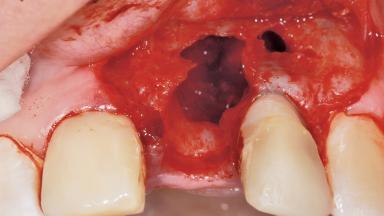

Late Placement of an Implant in a Maxillary Left Central Incisor Site

A 36-year-old female patient was referred for the replacement of the upper left central incisor (tooth 21), which had fractured. Although the tooth had been asymptomatic for many years, the crown began to loosen, at which time she presented to her dentist for an assessment. Teeth 21 and 22 had both been endodontically treated many years previously. She was a healthy individual and a non-smoker.

Bone Augmentation Horizontal|Staged

Augmentation Materials Xenogenous|Membrane

Soft Tissue Grafting Simultaneous

Bone Volume Deficient horizontally, requiring prior grafting